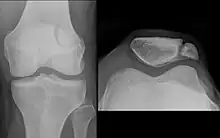

A vertical patella fracture with the fracture line marked by a black arrow

Diagnosis is based on symptoms and confirmed with X-rays.[3] In children an MRI may be required.[3]